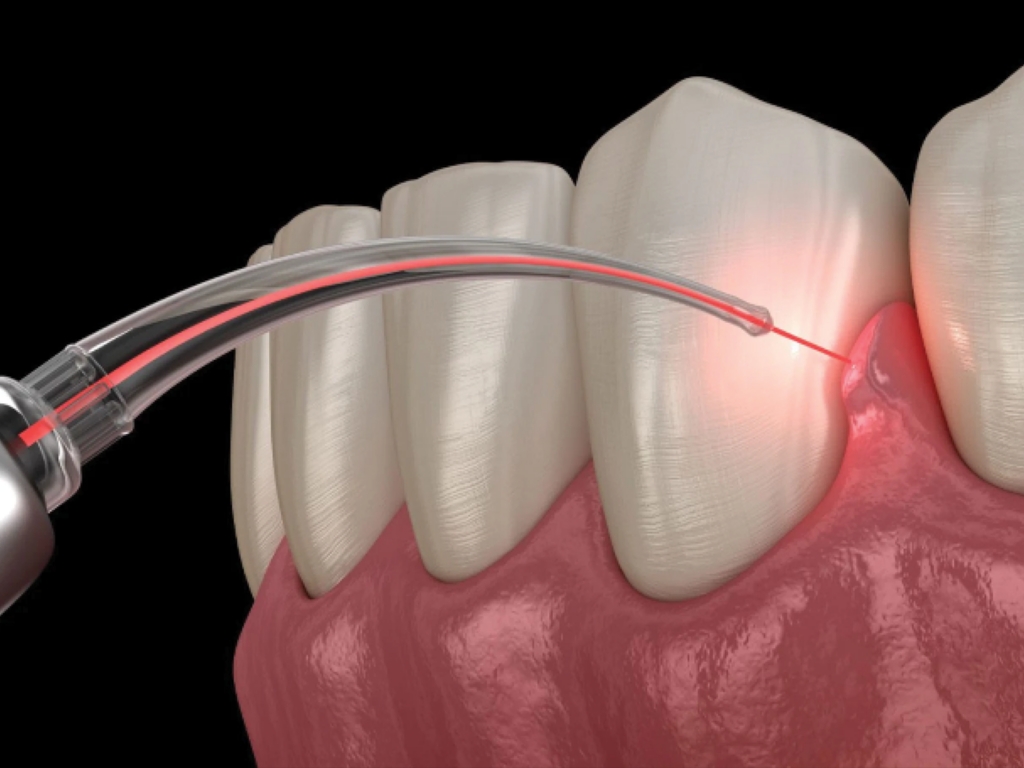

Gingivectomie

Remodelage de la gencive pour corriger un excès gingival, améliorer l’esthétique et faciliter l’hygiène selon indication.

Frénectomie

Intervention sur le frein (lèvre/langue) lorsqu’il gêne la fonction, l’orthodontie, ou favorise certains problèmes.

- Une gêne gingivale (excès de gencive, inflammation) selon indication

- Un frein (lèvre/langue) gênant ou limitant (parole, hygiène, orthodontie)

Frénectomie : à quoi ça sert ?

-Elle est indiquée quand le frein gêne la fonction (ex : traction, hygiène, orthodontie) selon l’examen.